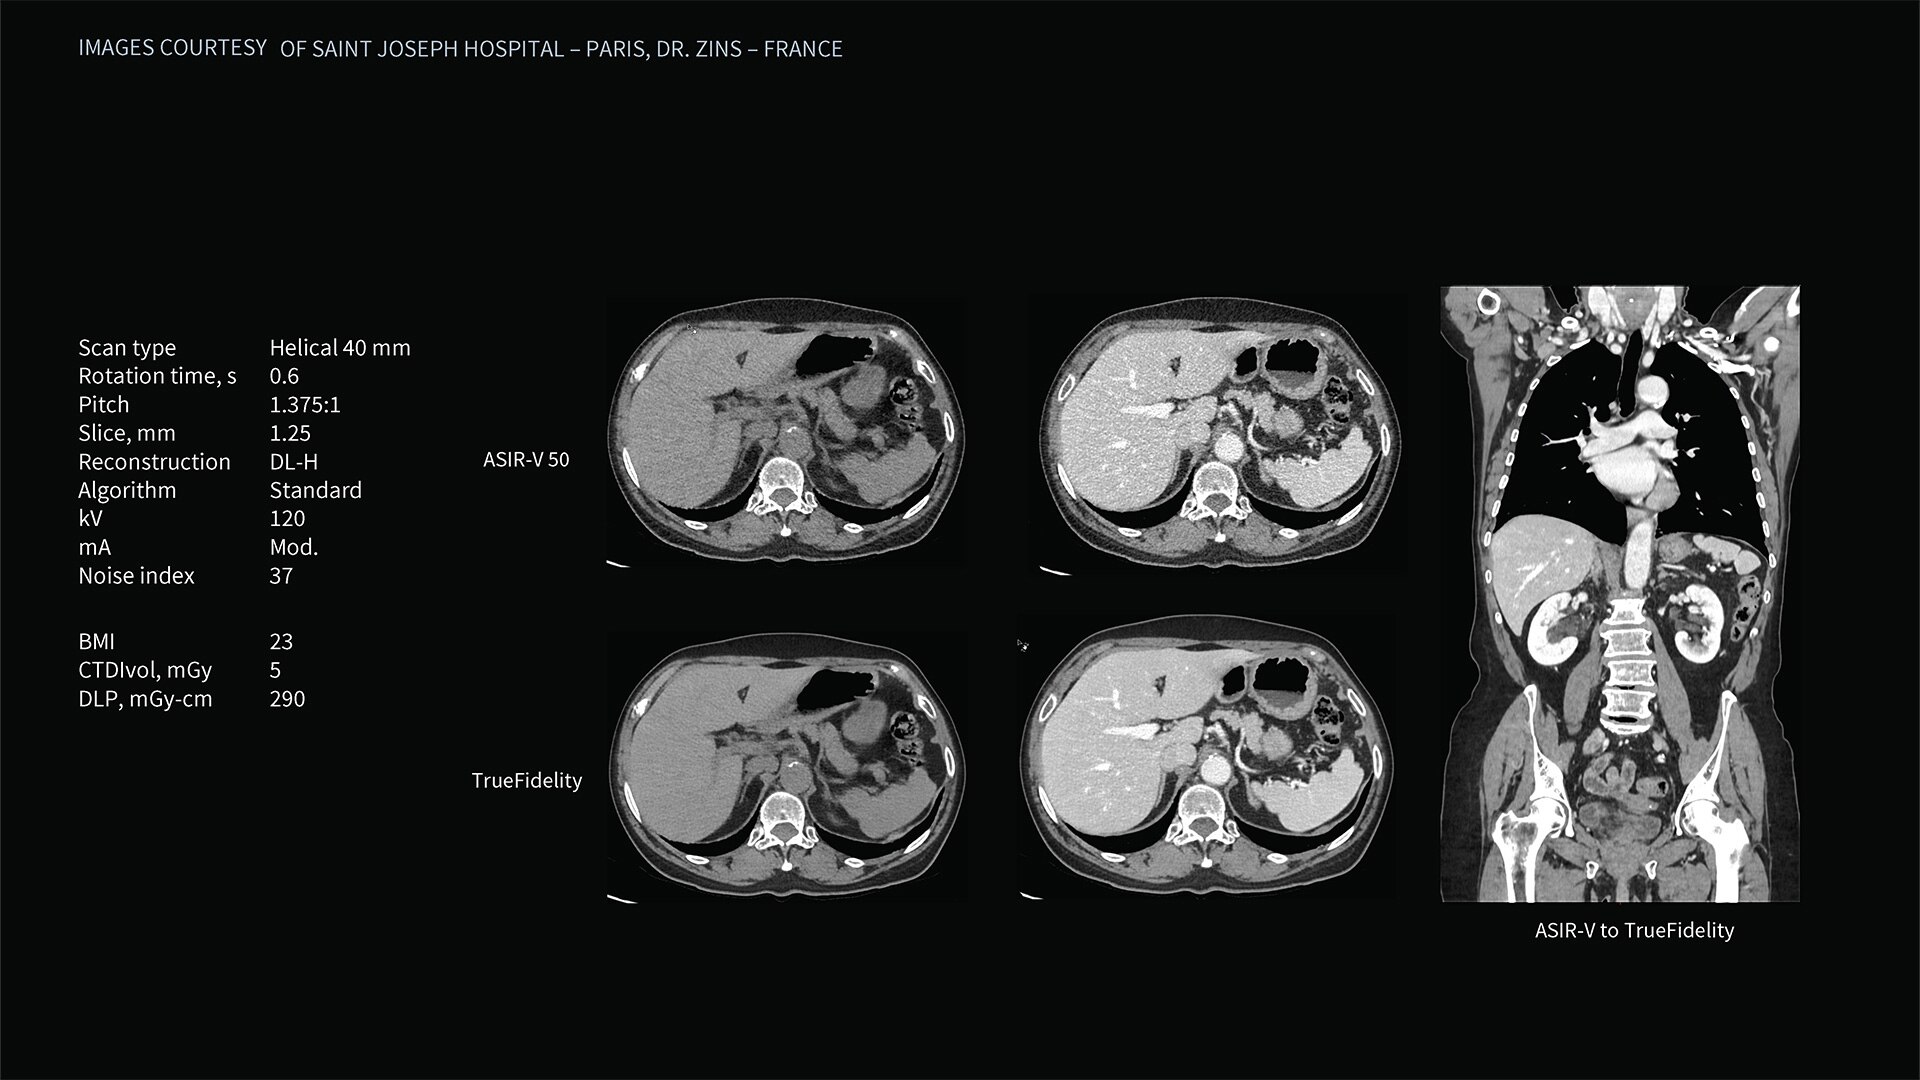

Deep learning image reconstruction, higher special resolution at 0.23 mm

Address individual clinical needs, moving seamlessly from one scan mode to the next. Image with a stunning 0.23 mm spatial resolution, then switch to rapid kV switching for full 50 cm FOV spectral imaging of the entire body. Choose up to six times reduction in motion artifact using SnapShot Freeze 2¹ for coronary artery CTA and reduce all-round dose with next-generation iterative reconstruction.